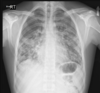

80 Mulher, Tosse

Consolidação com cavitação em lobo superior direito

Consolidação em lobo superior direito com áreas de cavitação

Padrão de micronódulos centrolobulares com árvore em brotamento

TB pós primária.